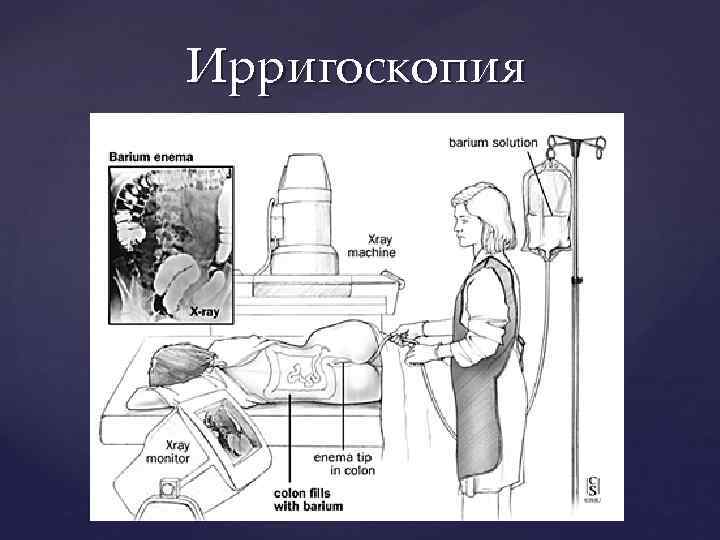

Колоноскопия